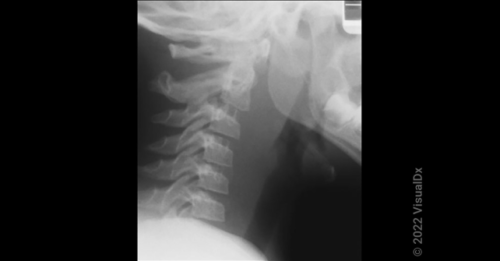

Answer: The correct answer is retropharyngeal abscess (d). A retropharyngeal abscess (RPA) is an uncommon but serious…